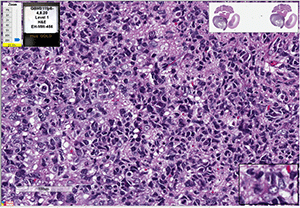

The figure at right depicts the best-characterized models for comparison. Click on it for a larger version.